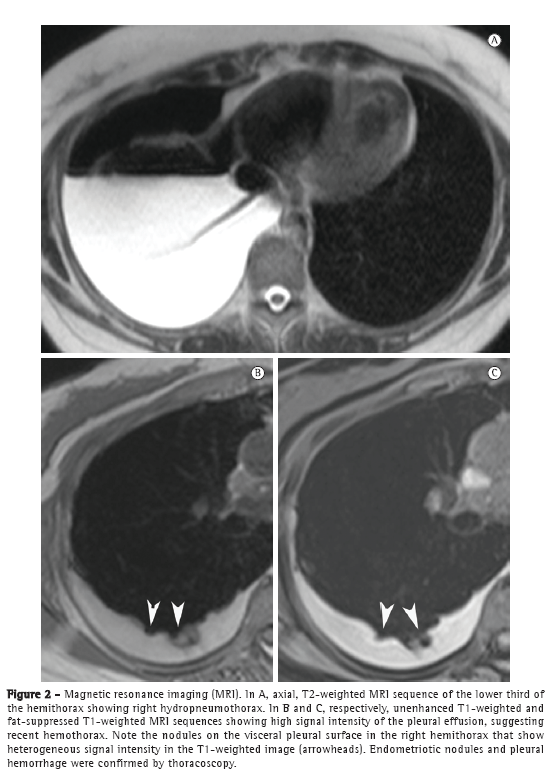

The patient underwent CT, which revealed right hydropneumothorax without focal lesions. On MRI scans of the chest, T1- and T2-weighted sequences showed right hydropneumothorax with hyperintense small nodular lesions (Figure 2), which are suggestive of endometriomas.

In recent years, MRI of the chest has progressed markedly. Because of improvements in speed and image quality, MRI is now ready for routine clinical use.(7-9) In both of the cases presented here, chest MRI revealed hydropneumothorax and well-defined, rounded nodules on the pleural surface in the right hemithorax. In Case 1, the pleural effusion had intermediate signal intensity on T1-weighted images, suggesting high protein content, probably related to hemorrhagic products. In Case 2, the pleural effusion had high signal intensity, suggesting recent hemothorax. The pleural nodules observed in Case 1 showed homogeneously high signal intensity on fat-suppressed T1-weighted images and restricted diffusion on diffusion-weighted imaging (DWI). In Case 2, the nodules showed heterogeneous signal intensity on T1- and T2-weighted images, without diffusion restriction. As in pelvic endometriosis,(1,10) pleural nodules of thoracic endometriosis might show different signal intensity on T1- and T2-weighted images, as well as variable diffusion restriction, depending on the age of the lesion.